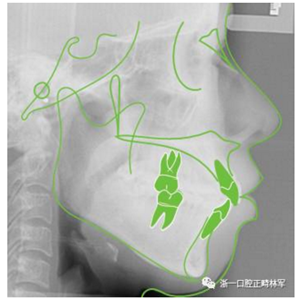

一個24歲的女生,覺得自己嘴巴太凸來矯正,她說小時候父母覺得她牙齒挺齊的沒必要矯正,所以現(xiàn)在才來(這里林醫(yī)生要提醒各位家長朋友,好的正畸醫(yī)生會全盤考慮面部骨骼、關(guān)節(jié)、肌肉、牙齒的和諧與美觀,不僅僅是排齊牙齒而已,孩子生長發(fā)育高峰之前治療,我們可以適當干預面部生長,達到臉型美觀事半功倍哦)。我們給這個女生仔細檢查了面部、牙齒、X光片,發(fā)現(xiàn)她的問題主要上下頜骨前突、頦部(即下巴)后縮,閉口時頦肌緊張,微笑時露齦笑。

以下是我們對初診病人的專業(yè)測量分析(不要再要求我們看一眼就給出治療方案啦):

口外檢查

正面分析:面部左右基本對稱,三等分正常;面下1/3過度飽滿;閉口時頦肌緊張。露齦笑,上唇弓形。

側(cè)面分析:側(cè)貌凸。上唇皮膚部分飽滿,鼻下點突。上下唇前突。

X線片檢查分析

初診全景片:牙齒數(shù)目形態(tài)未見異常,牙根未見異常。48近中阻生。

初診張閉口關(guān)節(jié)片:張閉口位關(guān)節(jié)間隙正常。雙側(cè)髁突外形正常,骨皮質(zhì)連續(xù),未見明顯吸收變形。

治療前側(cè)位片

頭影測量分析

Ricketts分析

Andrews六要素分析